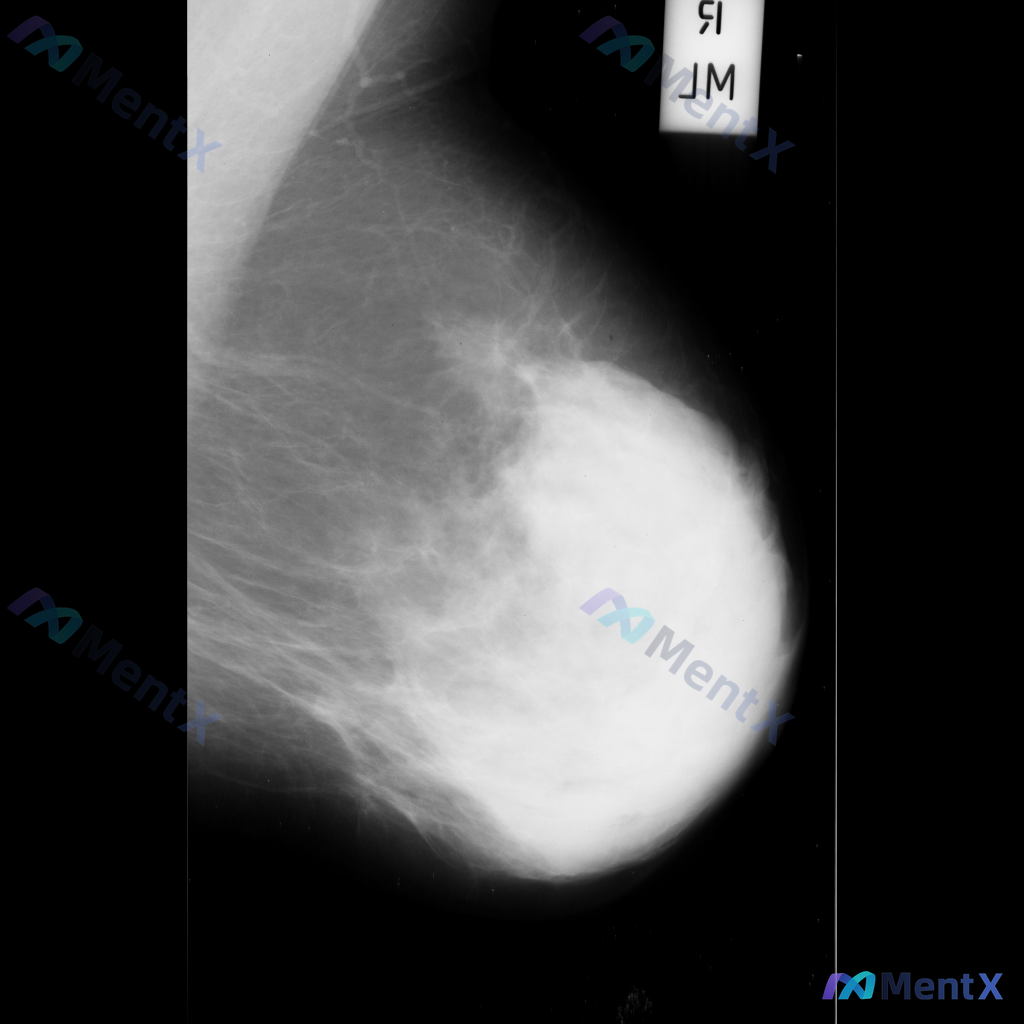

整理了一个乳腺钼靶读片的病例资料,大家可以一起讨论下性质判断的思路: 影像表现描述大致如下: - 乳腺中央偏上区域:可见不规则高密度影,密度较高,内部伴有粗大钙化,边缘不完全清晰; - 乳腺上部:可见类圆形高密度影,密度较高,边缘尚清晰但局部可能模糊; - 乳腺中部:可见数个散在的圆形或卵圆形结节影...

整理到一份乳腺钼靶的影像资料,大家可以一起讨论下: 主要影像表现:右侧乳腺后方(近胸壁处)可见一处局灶性不对称致密影,密度高于周围正常乳腺组织,边界模糊,同时伴有周围乳腺组织结构扭曲。 目前影像科考虑这处异常有可疑特征,需要进一步鉴别。 想问问大家,单看这组描述的话,第一反应会先往哪个方向考虑?后续...